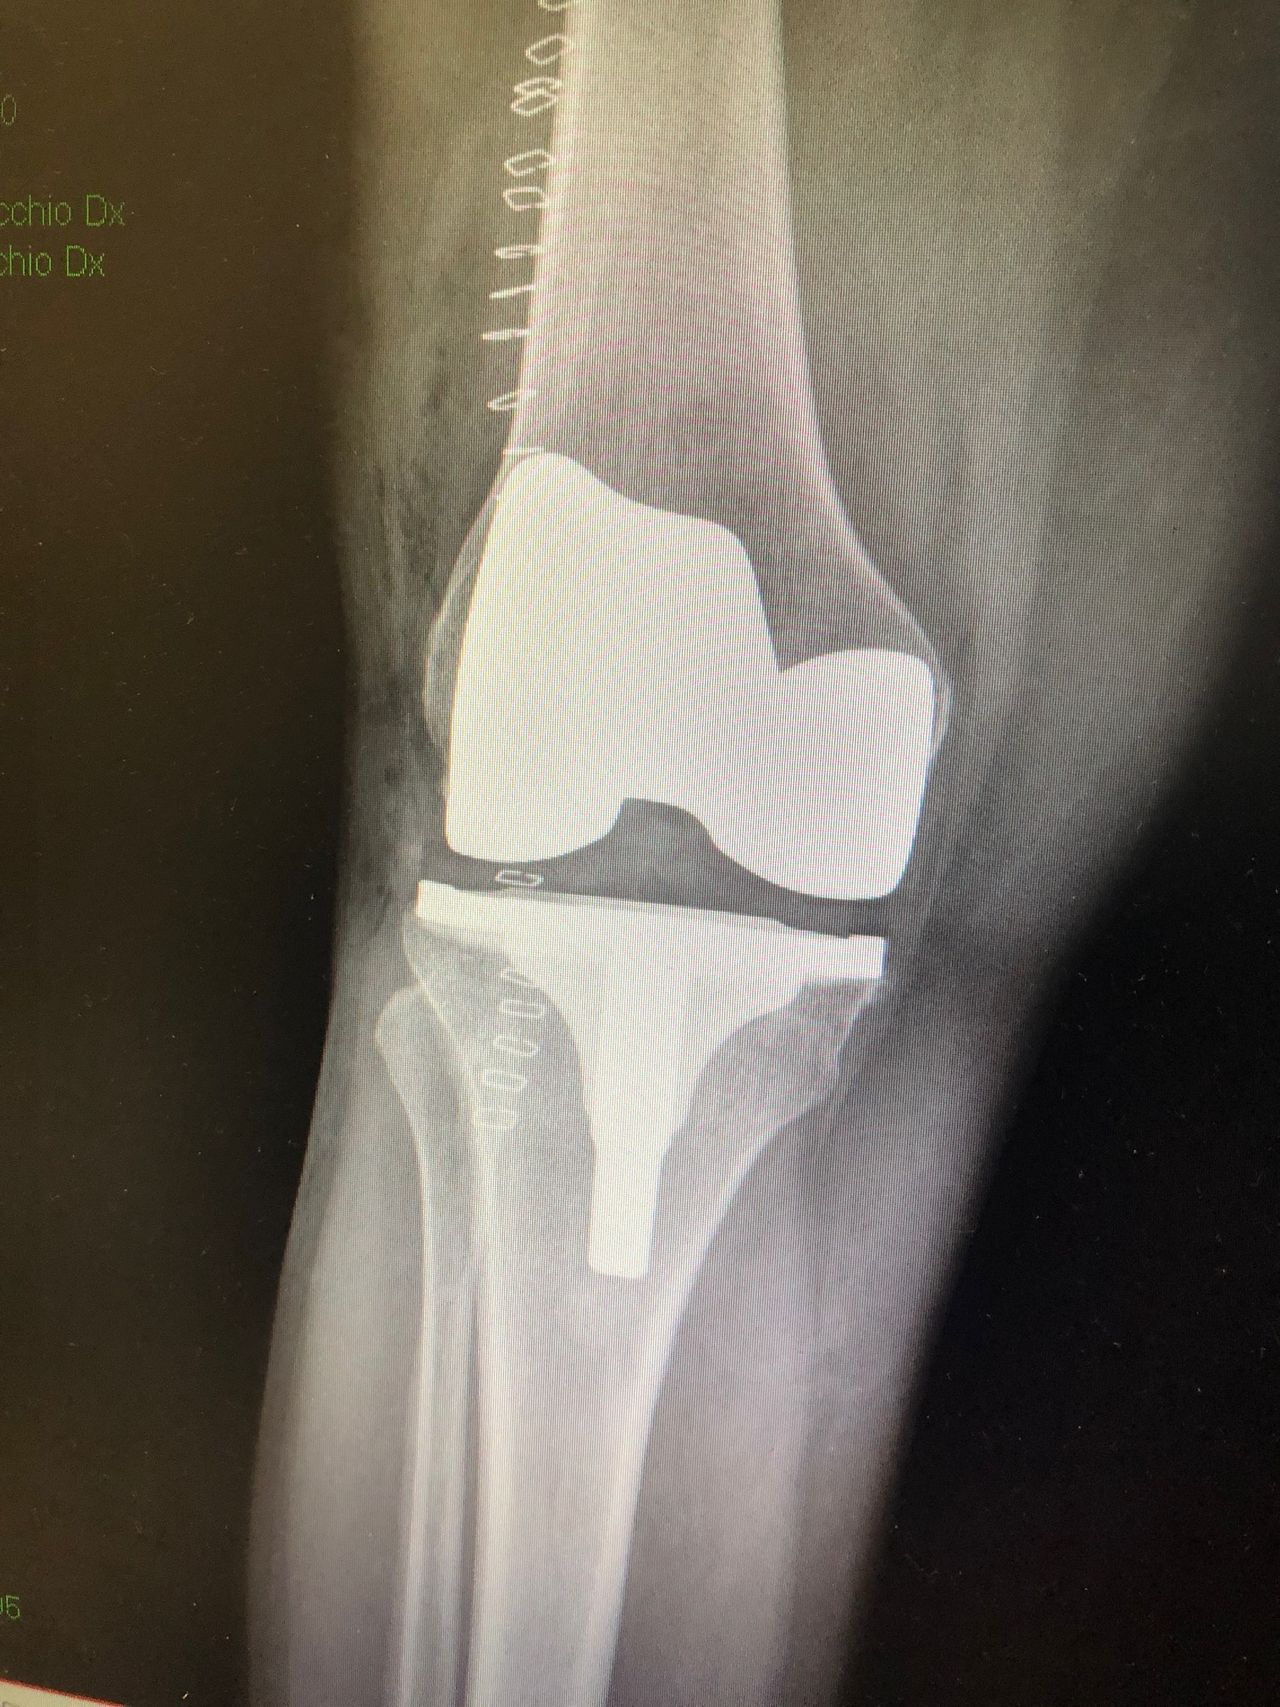

Sono specializzato nell'impianto di protesi di ginocchio ed anca in caso di patologie degenerative artritiche o necrotiche. Utilizzo protesi di ultima generazione, le protesi di ginocchio vengono applicate utilizzando una maschera creata su misura per ogni paziente, quelle di anca sono studiate per ridurre al minimo il rischio di lussazione (principale complicazione di questo tipo di intervento).

Salve, ho 54 anni e a giugno del 2019 ho fatto l'artoprotesi completa del ginocchio destro. Al controllo annuale ho fatto l'RX sotto carico in due proiezioni il cui referto è : "Protesi bicompartimentale apparentemente ben posizionata ed impiantata. Entesite calcifica del tendine quadricipitale".

Vorrei sapere se l'entesite si potrebbe risolvere in maniera spontanea o se è neccessario intervenire e come?